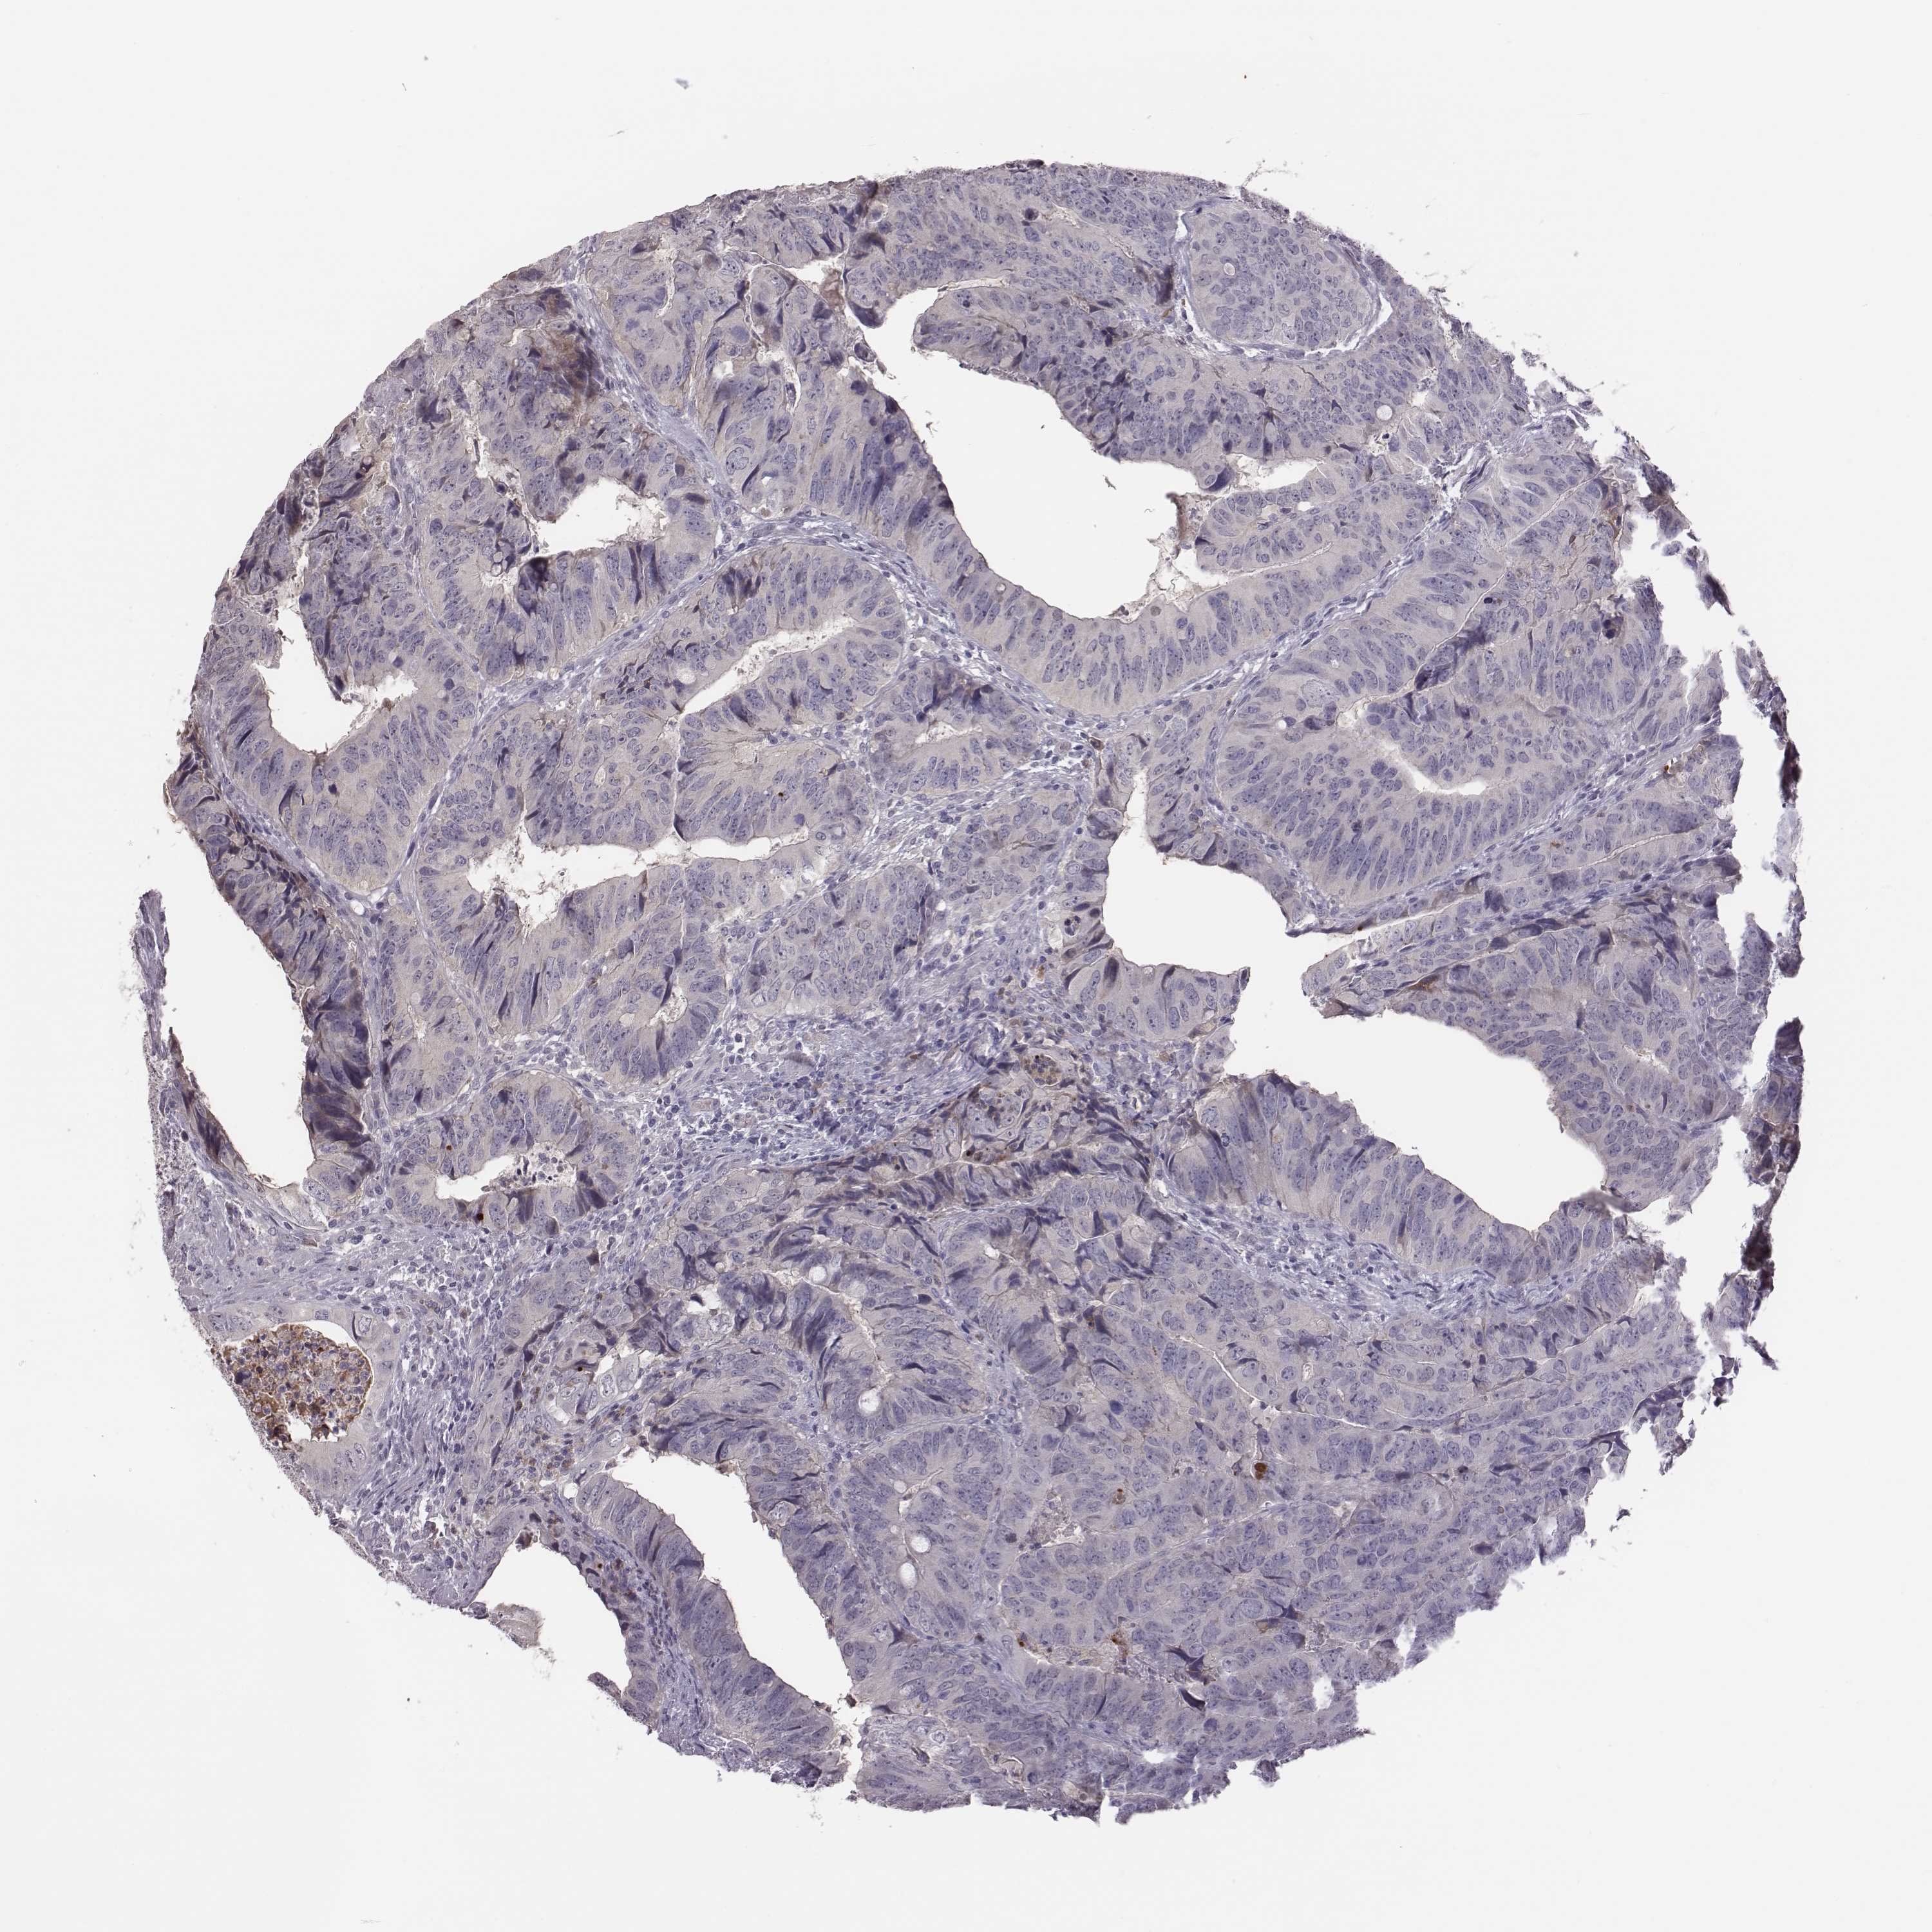

CANCER COLORECTAL CANCER Show tissue menu

Colorectal cancer

Human cancer